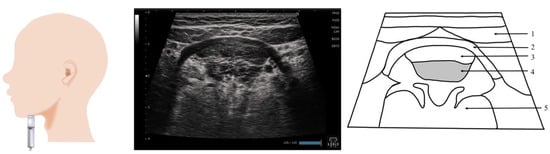

11. Pharynx (Figure 10 and Figure 11)